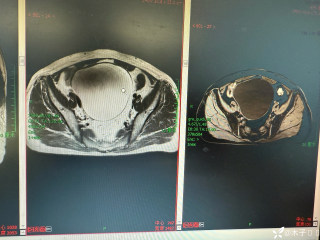

西地兰vip普外科医师

文/西地兰 特别声明:所有观点仅代表个人言论 特别声明:与当事双方均无利益相关 山东男孩,目前全网沸沸扬扬,看过一些观点,直言不讳地说,大多偏颇。要么一股脑地指责医方的全责,甚至有说千万别在县医院看病。要么又为医方无休止的遮羞,认为这样的手术在县医院做下来已经非常了不起。而我想到的是,以后面临类似的病例,我们怎么办?那么我们不如来一次专业的病案讨论。既然是事后讨论,难免有事后诸葛亮的感觉,但是假如下一次,同行们遭遇这样的病例,如何处置?这是医疗行业所面临的问题。希望我整理的这些思路和相关病例,对同行们有所帮助!就目前的资讯外界不足以判断是否需要急诊,如果需要急诊,那么只能根据术中所见进行处理,

智商不太富裕 回复

目前知道的消息,第一,术前发现一个血肿,然后做增强CT发现一个占位,没说血肿与肿瘤的关系,术后病理没有描述肿瘤出现破裂出血,大概率就一个小血肿,我就不明白当地主任凭哪个指针去给这小孩开急诊刀的?哪个指南告诉他需要急诊开?第二,诊断不明确他想的不是进一步检查,一边观察一边进一步查,他反而选择腹腔镜探查,这个探查的指针在哪?第三,腹腔一个血肿,没有活动性出血,没有血压心率出现问题,为什么要开腹进去碰它?不能等血肿吸收再明确肿瘤性质吗?第四,1点进腹,3点病理结果出来,按这个时间还算顺利,应该还没出事,孩子还算平稳,病理是低度恶性,切了就治愈,他一年能开几台这手术,就敢继续做,拿孩子练手。第五,后面